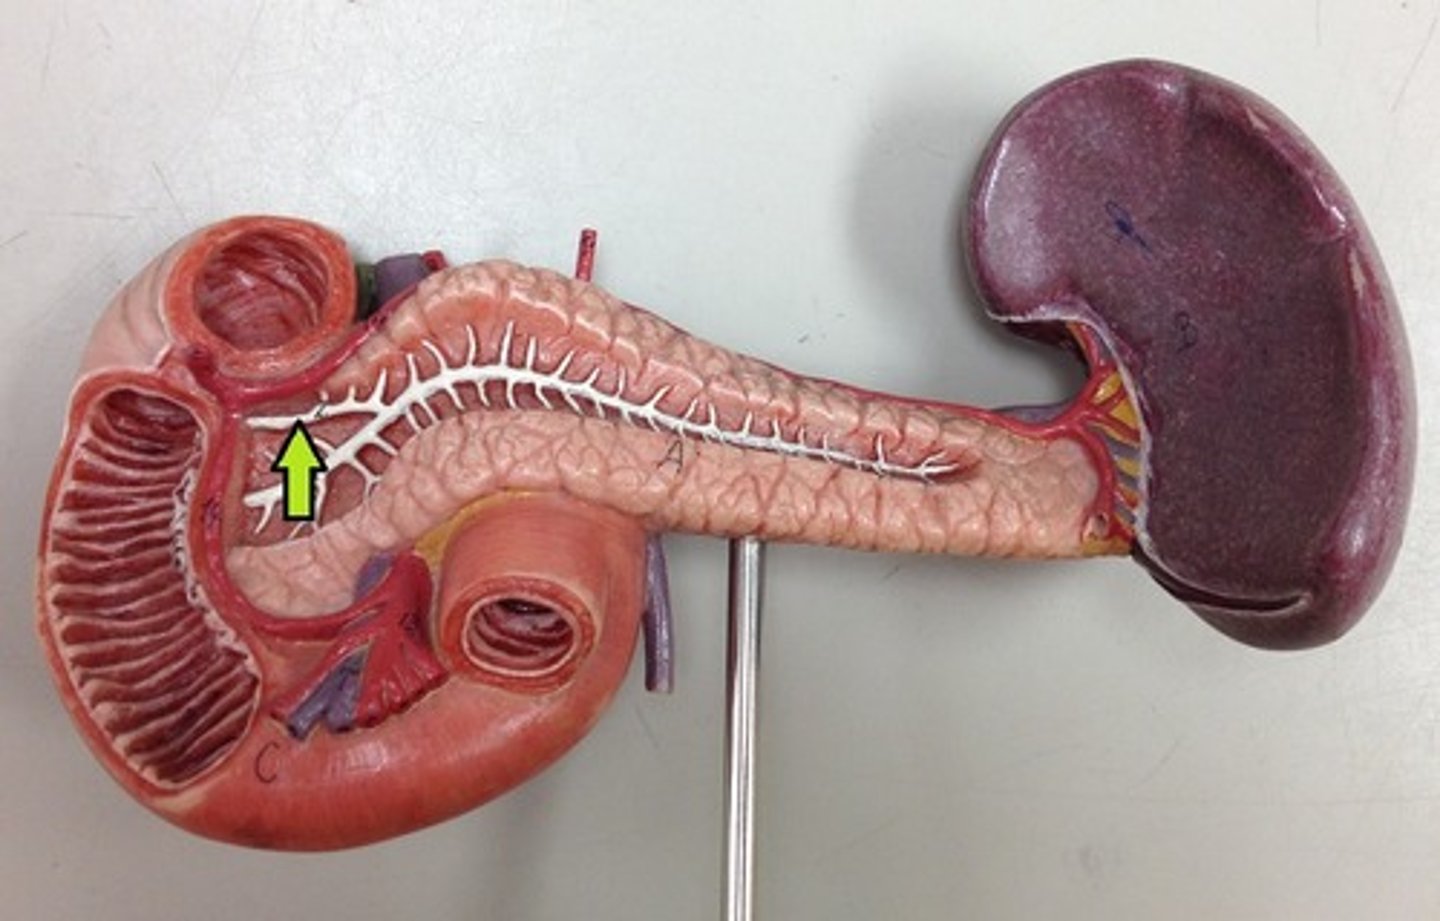

head (of pancreas)

body (of pancreas)

tail (of pancreas)

main pancreatic duct

accessory pancreatic duct

diaphragmatic surface (of spleen)

spleen

visceral surface (of spleen)

hilum (of spleen)

splenic vein

splenic artery